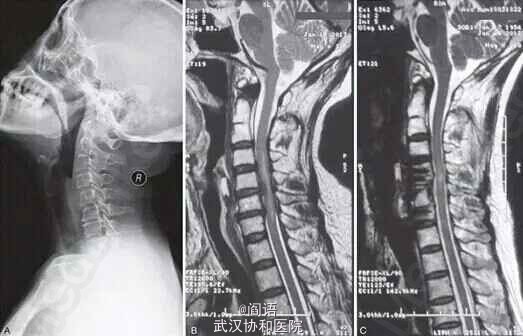

患者,女,60岁,主诉颈肩部疼痛 3 月,四肢肌力正常,无神经症状,行颈椎正侧位片检查后当地医生建议行按摩理疗。病人接受按摩后,疼痛缓解。一月后,例行体检发现甲状腺肿瘤,因不能排除恶性可能,择期于全麻下行甲状腺大部切除,手术进行顺利,耗时约100 分钟。恢复自主呼吸后,患者被送回病房。

术后两小时发现,病人四肢瘫痪,上肢肌力2级,下肢肌力1级。 急诊颈椎MRI提示:1.颈椎 C4-5,5-6,6-7 椎间盘突出压迫脊髓,2.脊髓内有缺血、坏死(C4-C7),3.颈椎2、3分节不全(Klippel Feil syndrome,先天性颈椎融合畸形)。

甲状腺切除术后约24小时,急诊再次行C6 椎体次全切、减压植骨融合术,病人术后神经症状明显好转;2周后肌力恢复正常,复查MRI提示脊髓减压充分。

本病例属于非脊柱手术并发的脊髓损伤,导致患者瘫痪。分析原因,患者术前颈椎片提示C6-7椎间盘病变;行甲状腺手术中,颈部过度后伸,导致椎管容积减少,并且加重椎间盘突出。